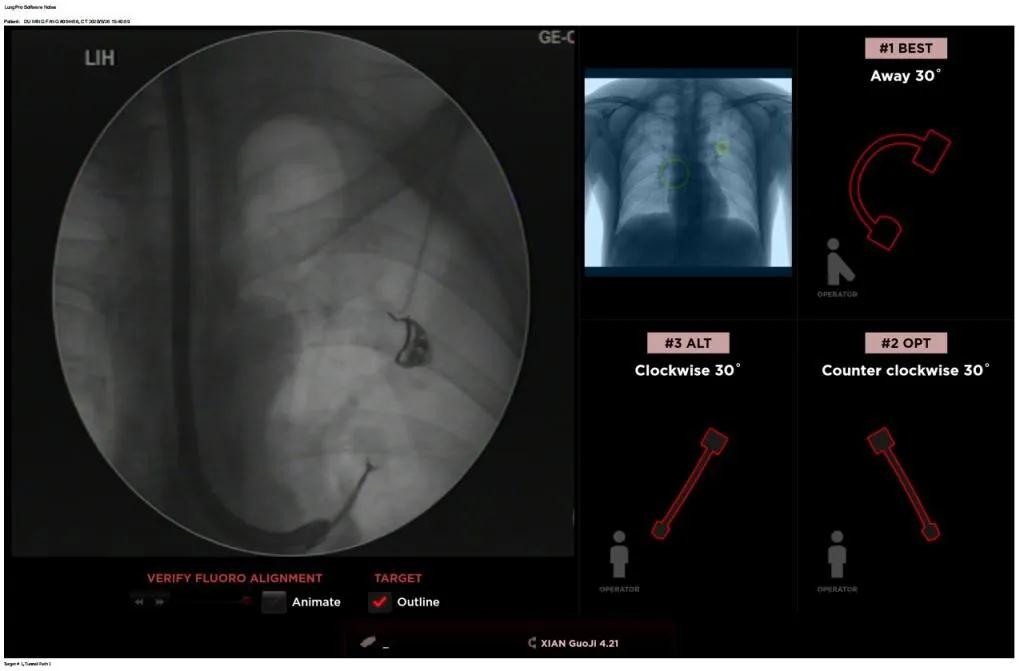

近日,西安國際醫(yī)學(xué)中心醫(yī)院胸科醫(yī)院歐陽海峰副院長完成西北地區(qū)首例LungPro全肺導(dǎo)航系統(tǒng)引導(dǎo)下經(jīng)支氣管鏡跨肺實質(zhì)肺外周結(jié)節(jié)活檢術(shù)。

經(jīng)過充分的討論后,歐陽海峰副院長決定為患者實施LungPro全肺導(dǎo)航系統(tǒng)引導(dǎo)的經(jīng)支氣管跨肺實質(zhì)肺外周結(jié)節(jié)活檢術(shù)。Broncus導(dǎo)航系統(tǒng)LungPro具有全球領(lǐng)先獨創(chuàng)的BTPNA技術(shù)(支氣管鏡下跨結(jié)節(jié)抵達(dá)術(shù)),可以實現(xiàn)對氣道外周孤立性肺小結(jié)節(jié)的精準(zhǔn)定位,建立直接通往氣道外病變部位的通道,以實現(xiàn)全肺的診斷及后續(xù)治療。這項技術(shù)不僅彌補(bǔ)了現(xiàn)有支氣管鏡技術(shù)由于受限于病變部位是否有氣道可通向以及無法準(zhǔn)確定位病變部位而造成的較低診斷率,同時還彌補(bǔ)了CT引導(dǎo)下經(jīng)胸穿刺(TTNA)無法適用于某些特定部位如中央及肩胛骨等結(jié)節(jié)的問題,并且還避免了經(jīng)胸穿刺給患者帶來氣胸、出血的高風(fēng)險,可有效提高肺部結(jié)節(jié)及早期肺癌診斷陽性率,亦可用于早期肺癌的射頻消融或微波治療,具有微創(chuàng)、安全、同期雙肺診療等優(yōu)勢。

BTPNA技術(shù)整合了虛擬導(dǎo)航支氣管鏡VBN、氣道內(nèi)超聲rEBUS、TBNA、高壓球囊擴(kuò)張、X線輔助等多項三、四級呼吸內(nèi)鏡技術(shù)。歐陽海峰副院長有3000 TBNA、1000 rEBUS、500 VBN、800 球囊擴(kuò)張方面的技術(shù)積累,10年來個人每年完成三、四級呼吸內(nèi)鏡手術(shù)1200余例,這有效保障了BTPNA技術(shù)的順利開展。

團(tuán)隊術(shù)前進(jìn)行了精心的準(zhǔn)備,通過高分辨率CT建立了導(dǎo)航路徑,在麻醉科手術(shù)室的配合下,借助LungPro引導(dǎo)順利的確定了病灶部位、建立隧道并實施活檢,術(shù)后患者恢復(fù)順利出院。